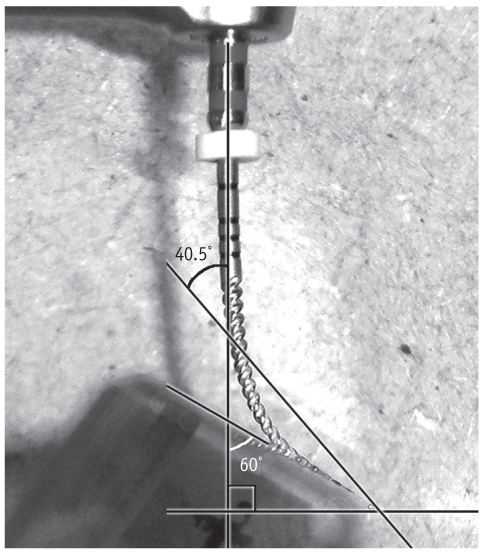

Time for separation of .06 taper ProFile